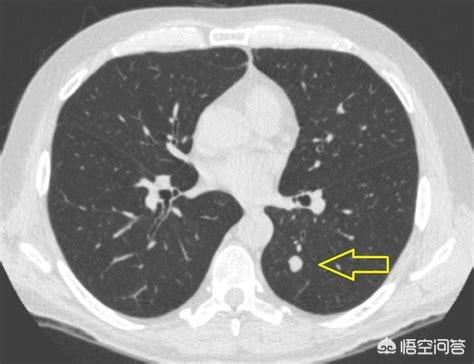

矢印は結節を指しているが、2016年3月に発見されたときは約0.5cmと非常に小さかったが、今では定期検診でこのように非常に多くの結節が見つかっている。画像で良性か悪性かを判断する方法はなく、検討するという選択肢しかなく、検討と経過観察も最良の手段である。

7ヵ月後、2016年10月の2回目の経過観察では、この結節がより大きく、丸みを帯びていることが明らかになった。経過観察時の結節の拡大は悪性腫瘍の可能性を警告するものであったが、この患者はそれでも手術を選択しなかった。